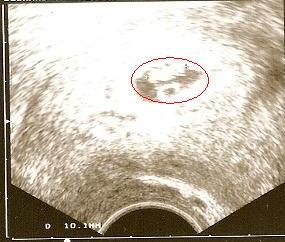

Aujourd'hui, 25 janvier, 16h30, papa et maman me découvre...

Je suis dans le petit roud rouge, pour que vous me voyez vous aussi

Je mesure 1 cm, j'ai déjà mon coeur et ma colonne vertébrale se forme bien.

Le seul souci, c'est les ovaires de maman. Au vue du kyste qu'elle a,

il faut qu'elle se tienne tranquille pendant les 3 prochains mois

Car si le kyste éclate, vous ne verrez jamais ma frimousse...

Je m'excuse pour elle pour toutes les soirées qu'il pourrait se prévoir

mais ce sera sans elle car moi je veux voir le jour,

normalement le 16 SEPTEMBRE.

Bisous à tous et rendez vous le mois prochain...